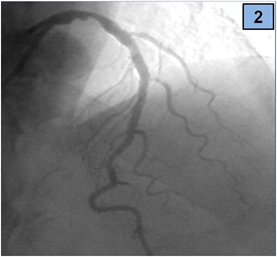

We present a 45-year-old man that was admitted to an emergency department with a history of sudden-onset, severe central chest pain associated with nausea and dyspnoea. Regarding cardiovascular risk factors, he was an active smoker (20 daily cigarettes) and had dyslipidaemia. On hospital arrival, he was lucid and oriented, had normal heart sounds and fine right basal inspiratory lung rales; arterial blood pressure was 120/70 mm Hg and heart rate 76 beats/min. The electrocardiogram showed sinus rhythm with ST segment elevation (4 mm in leads I and aVL, 2 mm in lead aVR), so emergent coronary angiography was indicated. The coronary angiogram showed an image suggestive of rupture plaque, that was located in the distal segment of the LMCA (Figure 1). There were also other lesions, a thrombotic total occlusion of the proximal circumflex (CX) artery and a severe stenosis of the proximal left anterior descending (LAD) artery (Figures 2 & 3). Right coronary artery was dominant with no lesions.

Figure 2 Severe distal LM and ostial LAD lesions with thrombotic occlusion of CX artery, cranial AP view.